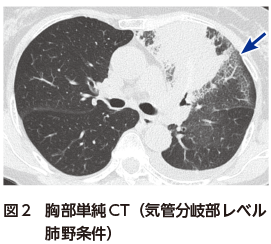

• A1:胸部単純X線写真で左上中肺野に浸潤影を認める(図1).

胸部単純X線写真では左上中肺野縦隔側に広範な浸潤影を認める(図1).胸部CTでは左上葉に,中枢から拡がる浸潤影を認め,周囲にすりガラス影を伴う(図2).胸部CT縦隔条件では,中枢気管支内に粘液栓を認め,内部のCT値が上昇している図3).いわゆる高吸収粘液栓(high attenuation mucus:HAM)の所見である.